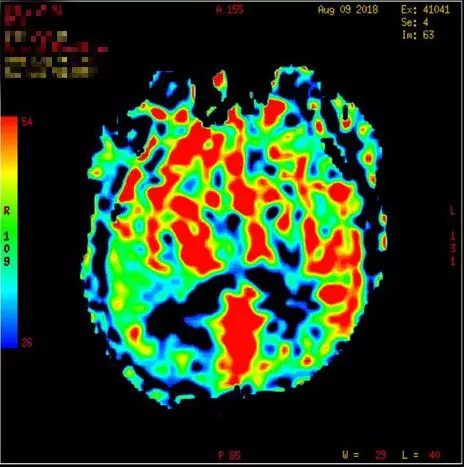

术后头颅MRI及ASL(08-09日 06:55分)